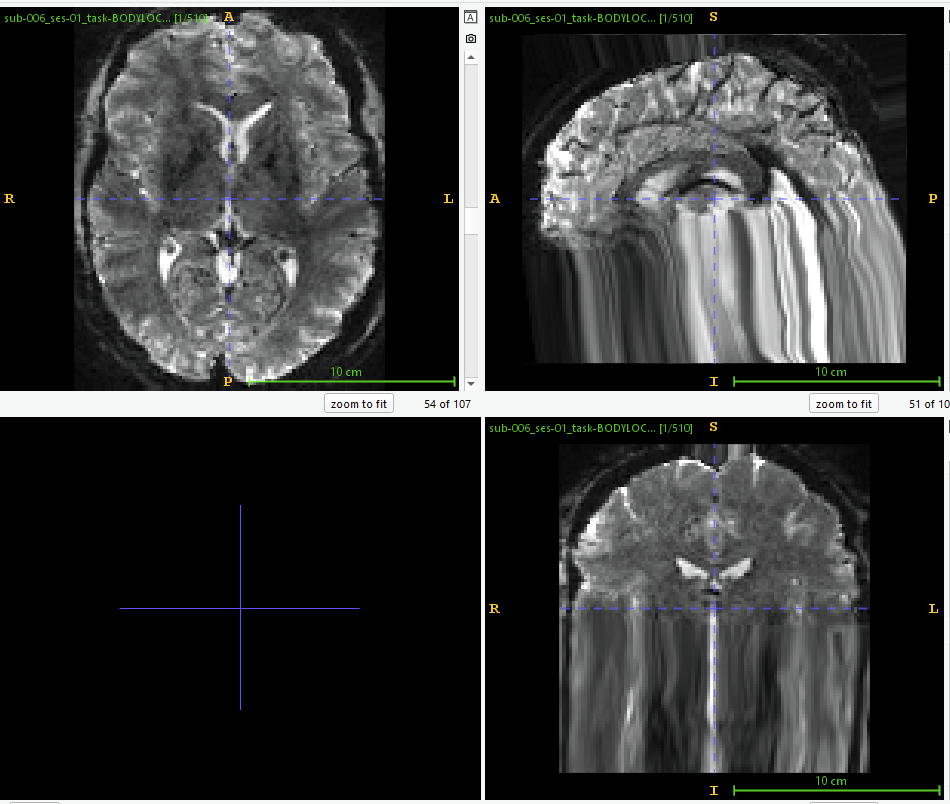

and a screenshot from ‘sub_ses_task-task_run-1_space-MNI152NLin2009cAsym_desc-preproc_bold.nii’ (using ITK Snap 4.2.2):